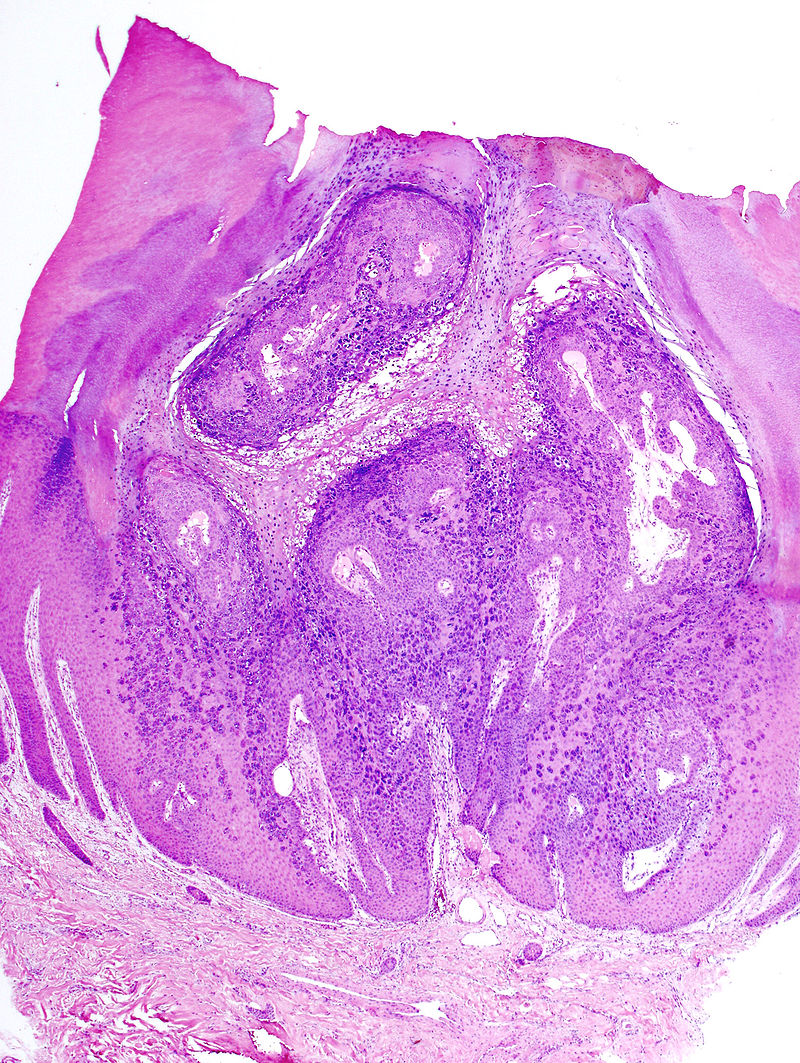

Come detto dunque la verruca è una formazione cutanea che nasce a causa della presenza del virus del papilloma umano: sono delle formazioni che non sono malevole ma che hanno un carattere benigno, e sono formate da due parti.

La prima esterna è composta da tessuto epiteliale, mentre il nucleo o parte interna della verruca è composta da un nucleo composto da un tessuto interno e che si alimenta con i vasi sangugni. Come avviene l’infezione in maniera molto semplice? Il virus entra in contatto con la pelle, penetra nell’epidermite e avviene l’infezione. Dopo aver descritto cosa è una verruca andiamo nel dettaglio a fare chiarezza su come possiamo evitarle ed il modo in cui si manifestano.